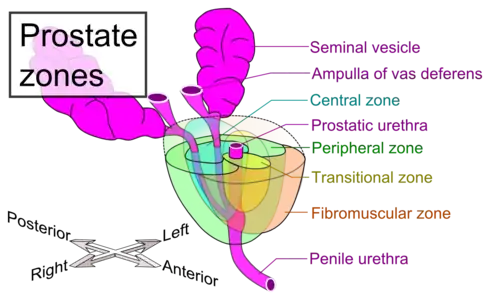

The internal structure of the prostate has been described using both lobes and zones.[4][1] Because of the variation in descriptions and definitions of lobes, the zone classification is used more predominantly.[1]

The prostate has been described as consisting of three or four zones.[1][3] Zones are more typically able to be seen on histology, or in medical imaging, such as ultrasound or MRI.[1][4] The zones are:

| Name | Fraction of adult gland[1] | Description |

| Peripheral zone (PZ) | 70% | The back of the gland that surrounds the distal urethra and lies beneath the capsule. About 70–80% of prostatic cancers originate from this zone of the gland.[5][6] |

| Central zone (CZ) | 20% | This zone surrounds the ejaculatory ducts.[1] The central zone accounts for roughly 2.5% of prostate cancers; these cancers tend to be more aggressive and more likely to invade the seminal vesicles.[7] |

| Transition zone (TZ) | 5% | The transition zone surrounds the proximal urethra.[1] ~10–20% of prostate cancers originate in this zone. It is the region of the prostate gland that grows throughout life and causes the disease of benign prostatic enlargement.[5][6] |

| Anterior fibro-muscular zone (or stroma) | N/A | This area, not always considered a zone,[3] is usually devoid of glandular components and composed only, as its name suggests, of muscle and fibrous tissue.[1] |

Lobes of prostate Zones of prostate

Zones of prostate